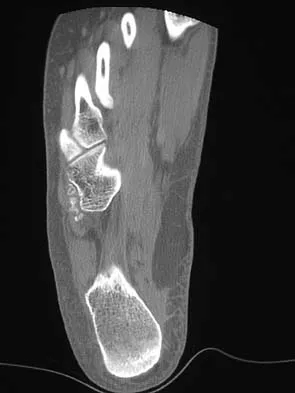

The oblique radiograph of the foot and the CT scan shown in Figures 10a and 10b show a patient whose symptoms have failed to respond to rest and non-steroidal anti-inflammatory drugs. What is the best course of action?

Explanation